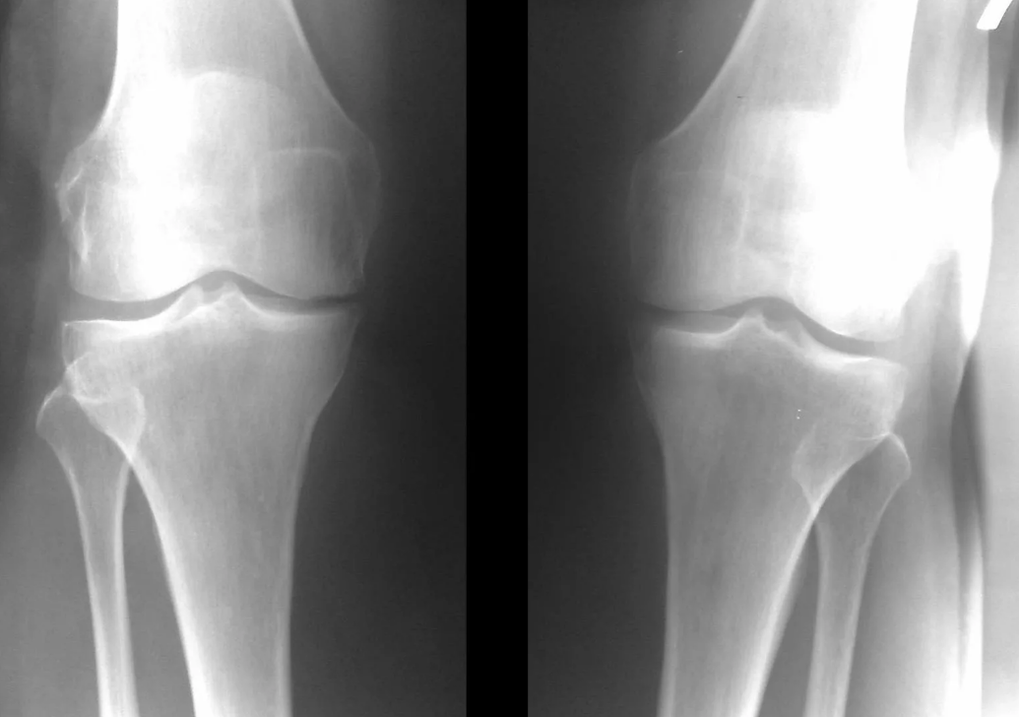

Instrumental diagnosis of arthrosis of the knee joint

In the majority of cases, an examination and an X-ray of the knee joint in two projections (direct and lateral) is sufficient.Clinical data and imaging help to determine the stage of the disease.

In the early stages of the disease, with minor changes in bone tissue, X-ray examination is not so valuable.At this stage, gonarthrosis can be diagnosed by arthroscopy.The accuracy of the method is very high;only its invasive nature and cost can stop it.

Ultrasound does not allow clear visualization of changes in the articular cartilage and intra-articular structures.With the help of MRI, you can detect changes in the bones, cartilage and soft tissue structures of the joint, as well as the subchondral bone with 85% accuracy.Scintigraphy can be used to assess the metabolic activity of periarticular bone tissue.